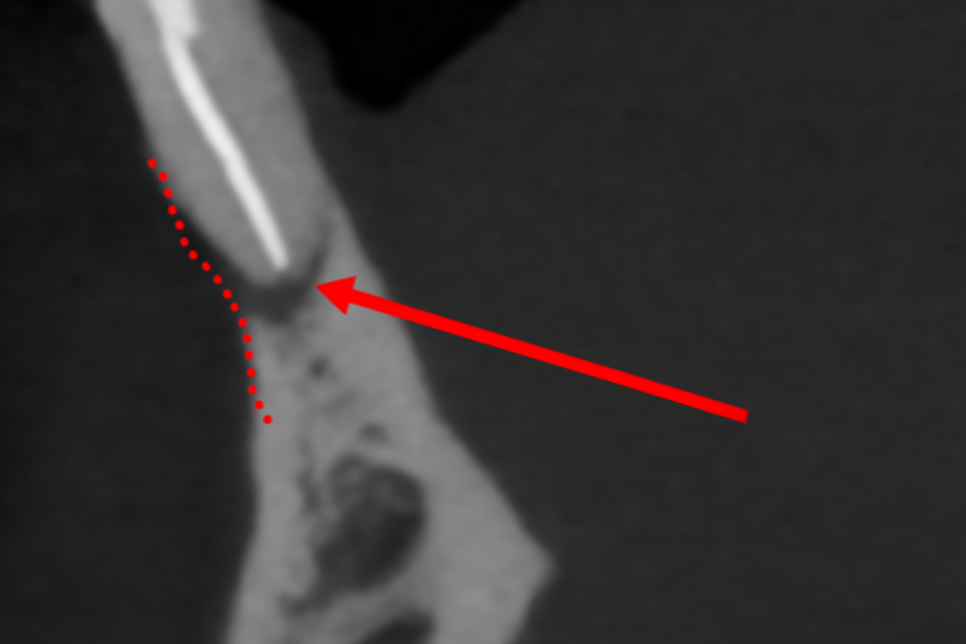

CT 촬영으로 뼈 상태와

치은 상태를 정확히 확인합니다.

뼈가 많이 녹았다면

이를 뽑을 때 또는

일정 시간 후에 뼈이식을 합니다.

Implant를 심을 때

정확한 위치가 중요하기에

각도와 위치, 깊이를

세밀하게 맞춰야 됩니다.